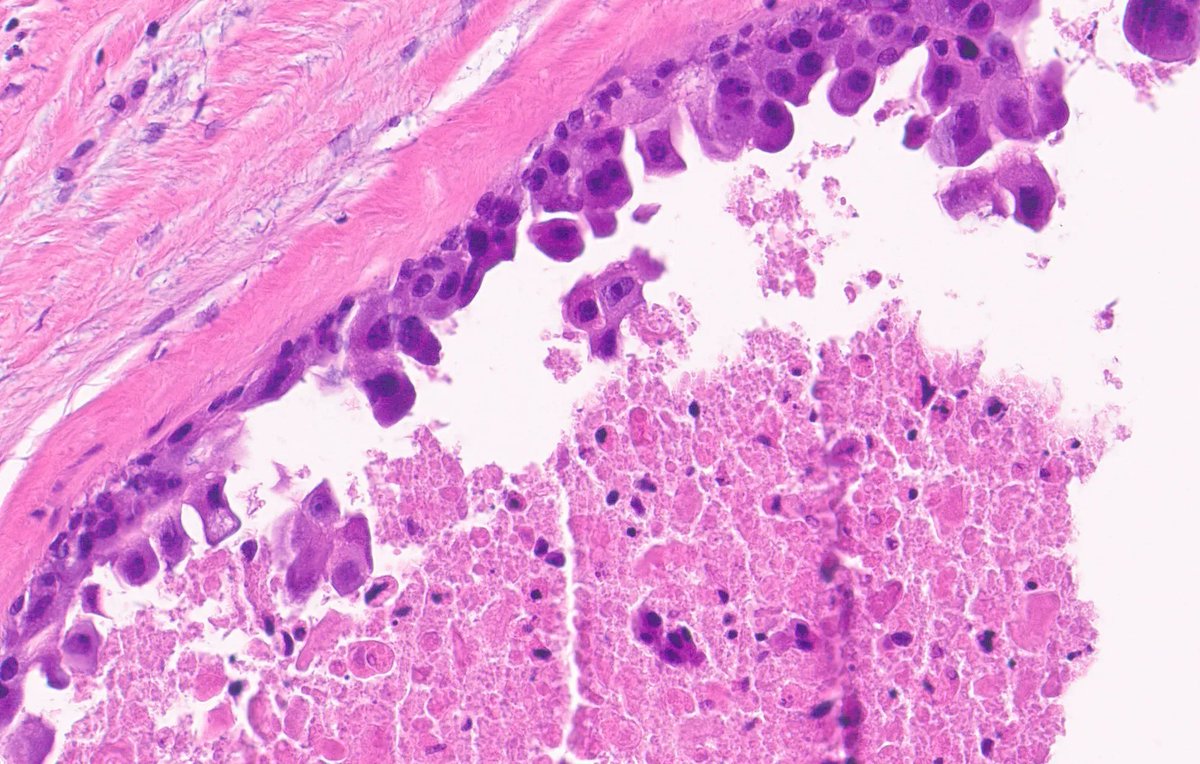

Young adult with lip lesion. Special stains negative. Diagnosis? Answer & More info: kikoxp.com/posts/9905 More posts from Dr. Rutland @TristanRutland7 kikoxp.com/tristan_rutlan… #pathology #pathTwitter #medTwitter #oralpath #ENTpath

kiko4docs's tweet image. Young adult with lip lesion. Special stains negative. Diagnosis?

Answer & More info: kikoxp.com/posts/9905

More posts from Dr. Rutland @TristanRutland7 kikoxp.com/tristan_rutlan…

#pathology #pathTwitter #medTwitter #oralpath #ENTpath